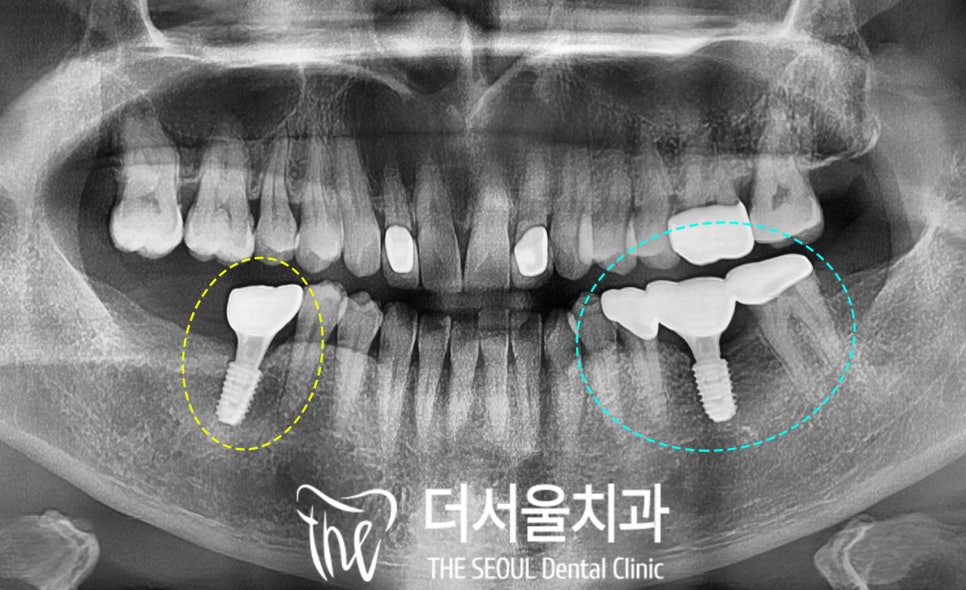

파노라마 엑스레이를 찍어 살펴보니

왼쪽 아래 (30번대)와

오른쪽 아래(40번대)의

어금니 결손이 확인되었으며

장시간 방치되어 있던 탓에

치조골도 많이 퇴축되어 있었습니다.

【 보철 수복 】

성남 치과의원 에서

3개월 정도 골 유착을 기다렸다가

어느 정도 고정력이 확보되면

최종 보철을 올려드립니다.

왼쪽 아래 30번대는

두 번째 작은 어금니부터 두 번째 큰 어금니까지

브릿지로 연결해 드렸는데요,

가운데 픽스처가 하나 더 생겼으니

이전보다 훨씬 더 안정된 느낌을

받으실 수 있을 겁니다.

교합면은 hole이 뚫어진 형태의

SCRP 타입으로 제작하여

추후 문제가 있을 시

수리를 용이하게 할 수 있도록

적용해두었습니다.